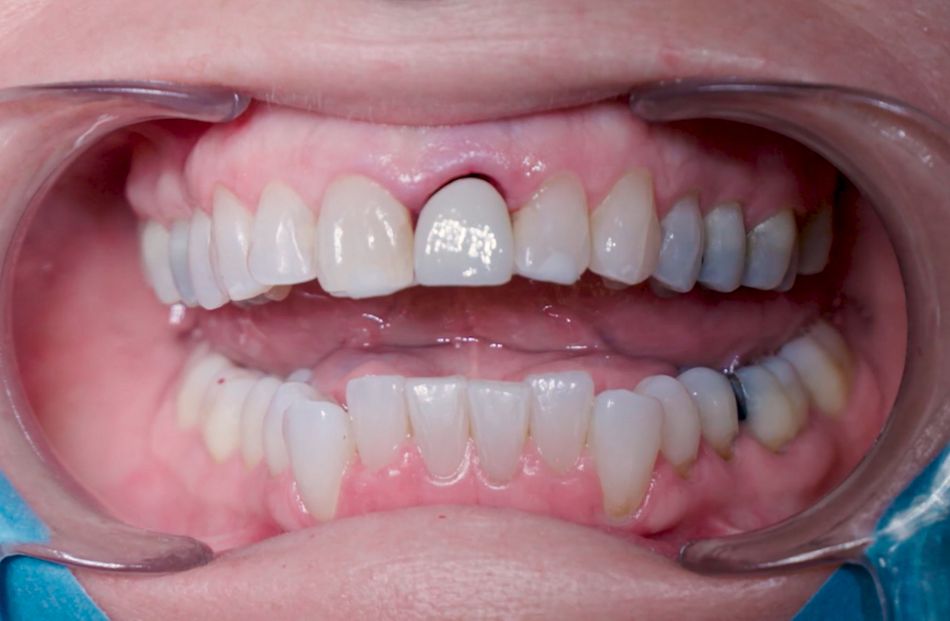

Женщина 53 лет обратилась в клинику по поводу сломанного центрального резца, который уже многократно восстанавливали керамической коронкой (Илл. 1, 2). По результатам сбора анамнеза и клинического осмотра стало ясно, что у пациентки хорошее состояние здоровья в целом и ротовой полости в частности, с хорошо сбалансированной окклюзией. Пациентка не курит. На конусно-лучевой компьютерной томограмме (КЛКТ) и периапикальной рентгенограмме стало очевидно, что у пациентки внешняя резорбция корня с очень небольшой ретенцией зуба в альвеолярной кости, из-за чего невозможно установить достаточный традиционный внутрикорневой штифт (Илл. 3,4).Учитывая то, что сломанный зуб находился в эстетически значимой зоне, пациентка попросила провести лечение максимально быстро и безопасно.